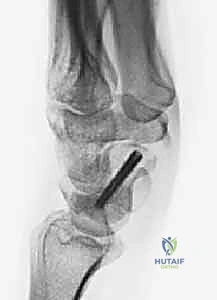

- الاستئصال الدقيق: باستخدام أدوات جراحية ميكروسكوبية دقيقة، يتم استئصال حوالي 3 إلى 4 مليمترات من القطب البعيد للعظم الزورقي. هذه الكمية كافية لمنع الاحتكاك مع عظم الكعبرة، وفي نفس الوقت تحافظ على استقرار الأربطة.

- تقييم المفصل: يتم فحص باقي عظام الرسغ للتأكد من عدم وجود خشونة متقدمة في أماكن أخرى.